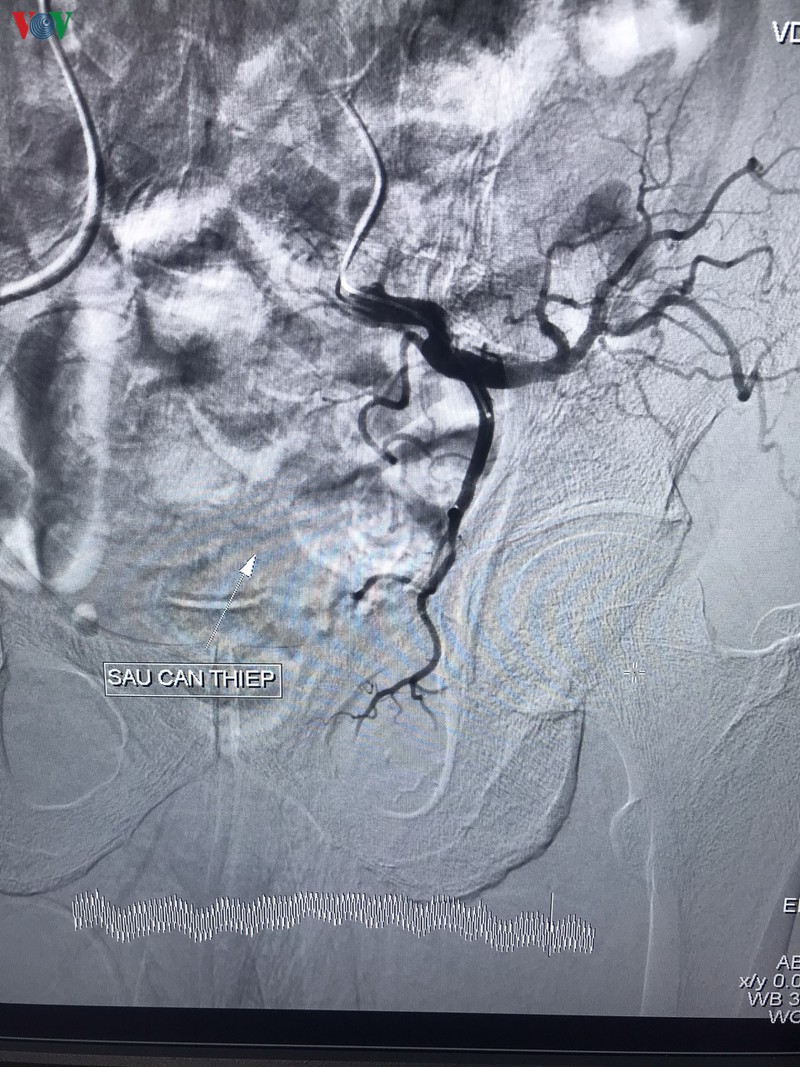

can thiep thanh cong benh nhan bi tieu ra mau nguy kich o can tho hinh 2

Bác sĩ thăm khám cho bệnh nhân.